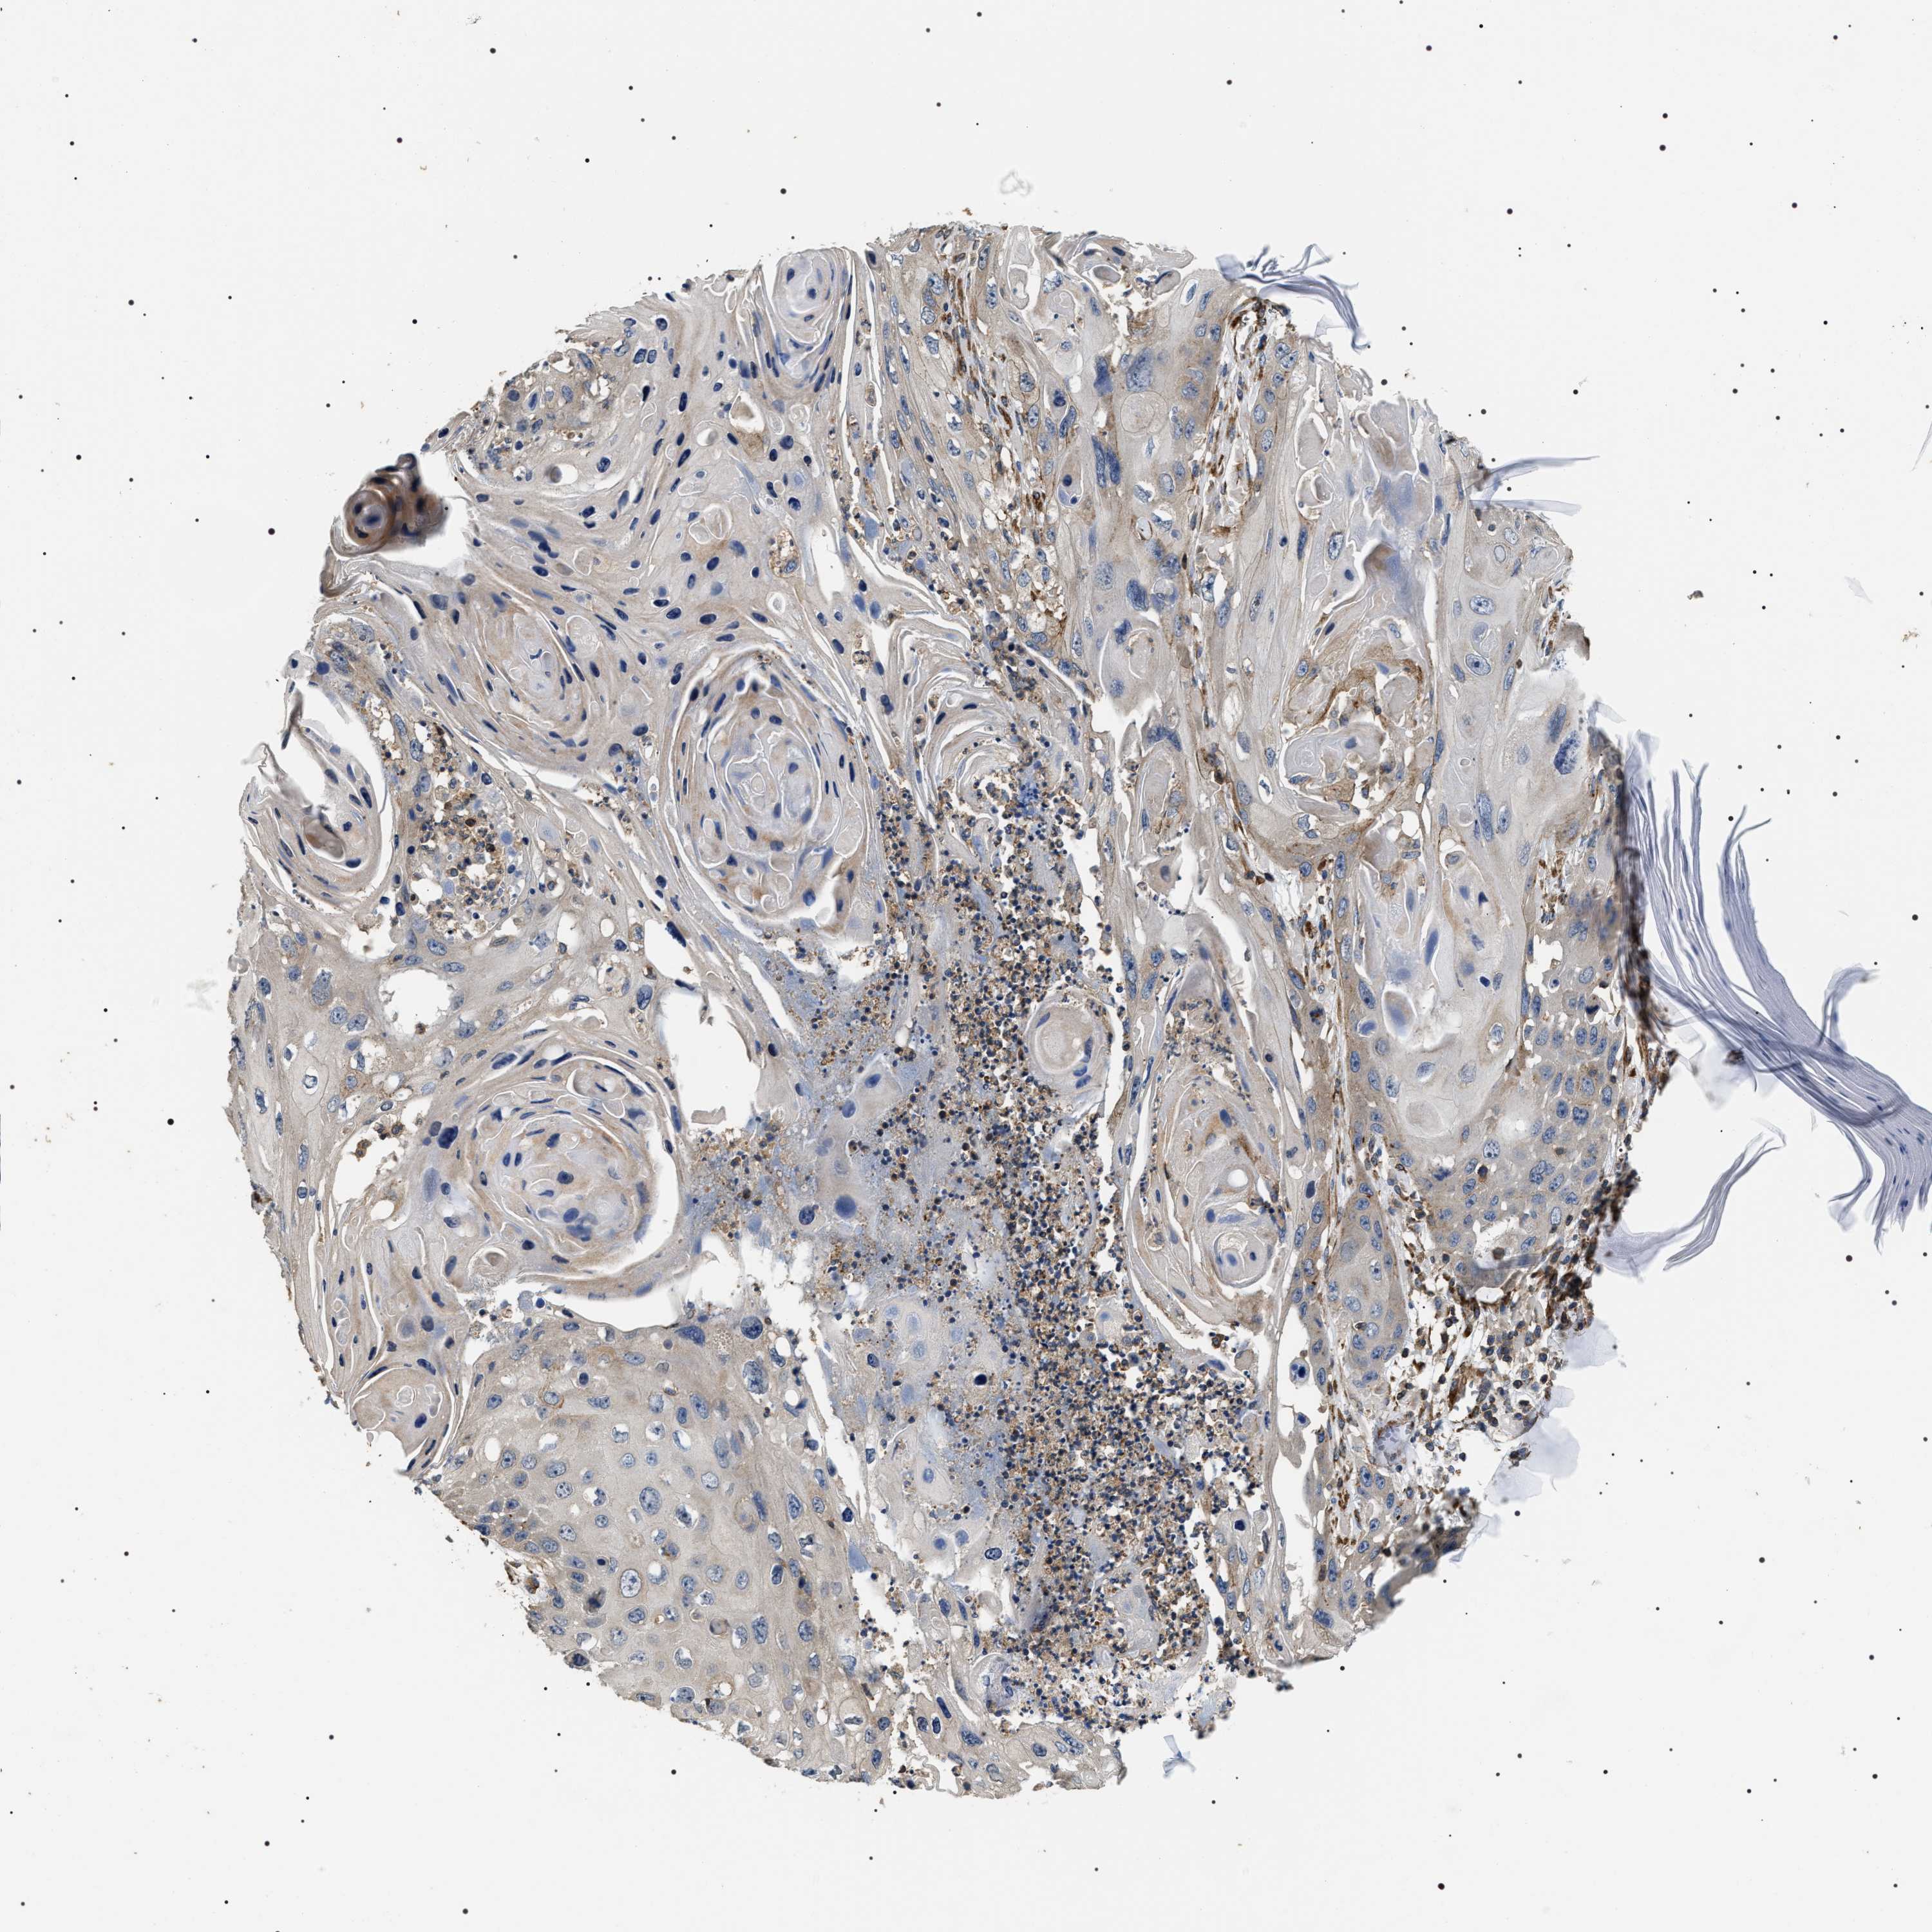

CANCER SKIN CANCER Show tissue menu

Basal cell and squamous cell cancer

SKIN CANCER - Protein expressioni

A mouse-over function shows sample information and annotation data. Click on an image to view it in a full screen mode. Samples can be filtered based on level of antibody staining by selecting one or several of the following categories: high, medium, low and not detected. The assay and annotation is described here.

Each image is clickable and will lead to virtual microscopy that enables deeper exploration of all samples and also displays staining intensity scores, fraction scores and subcellular localization as well as patient and tissue information for each sample.

Antibody HPA020386

Squamous cell carcinoma, NOS